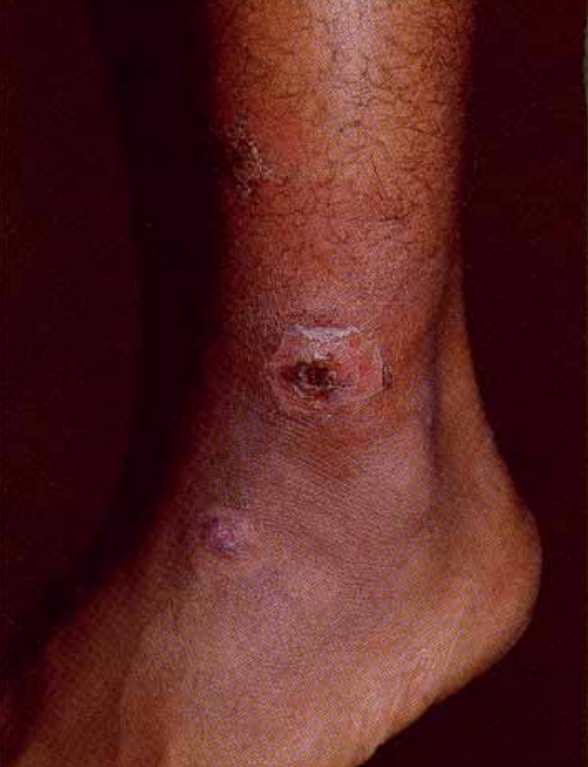

ENFEKTE YARA

Enfekte yaralar, mikroorganizma bulaşma olasılığı yüksek olan yaralardır.

Enfeksiyon oluşma riski yüksek yaralar şunlardır:

-Üzerinden 6 saat geçmiş yani gecikmiş yaralar,

– Kenarları düzgün olmayan yaralar,

-Cerrahi dikişleri ayrılmış yaralar,

-Çok kirli ve derin dokuların (damar, kas, sinir vb.) hasar gördüğü yaralar,

-Ateşli silahlarla meydana gelen yaralar,

-Böcek, yılan, köpek gibi canlıların ısırma ve sokmaları ile oluşan yaralardır.

CloseENFEKTE YARA

Enfekte yaralar, mikroorganizma bulaşma olasılığı yüksek olan yaralardır.

Enfeksiyon oluşma riski yüksek yaralar şunlardır:

-Üzerinden 6 saat geçmiş yani gecikmiş yaralar,

– Kenarları düzgün olmayan yaralar,

-Cerrahi dikişleri ayrılmış yaralar,

-Çok kirli ve derin dokuların (damar, kas, sinir vb.) hasar gördüğü yaralar,

-Ateşli silahlarla meydana gelen yaralar,

-Böcek, yılan, köpek gibi canlıların ısırma ve sokmaları ile oluşan yaralardır. -